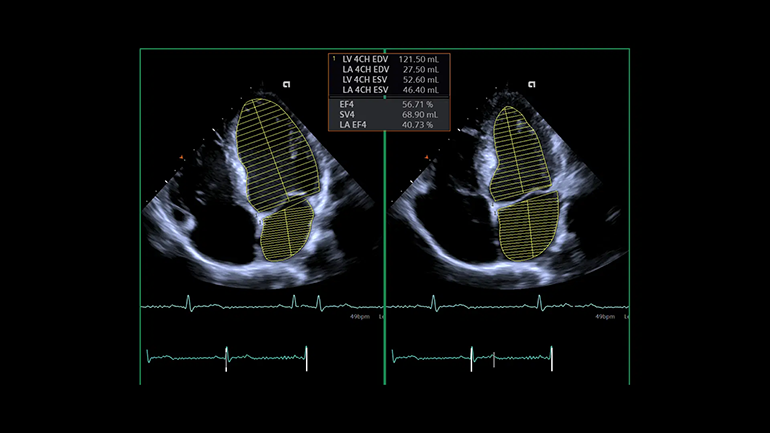

Технология автоматических перинатальных измерений eSie OB. eSie OB автоматизирует выполнение биометрических измерений при акушерских исследованиях. Она не только уменьшает время сканирования и сокращает количество нажатий клавиш, но и повышает воспроизводимость УЗ- исследований. Технология автоматического исследования левых отделов сердца eSie Left Heart. Технология eSie Left Heart идентифицирует и автоматически очерчивает левый желудочек и левое предсердие, благодаря чему повышаются согласованность и воспроизводимость количественного анализа этих отделов сердца.

Технология автоматического исследования левых отделов сердца eSie Left Heart. Технология eSie Left Heart идентифицирует и автоматически очерчивает левый желудочек и левое предсердие, благодаря чему повышаются согласованность и воспроизводимость количественного анализа этих отделов сердца.Портативные сканеры легкие (5-15 кг) и компактные (размером с ноутбук), активно применяются в ситуациях, требующих скорой медицинской помощи, как на выездах, так и внутри лечебного учреждения. В больнице переносные приборы часто устанавливаются на специальную тележку, оснащенную держателями датчиков и другими опциями.